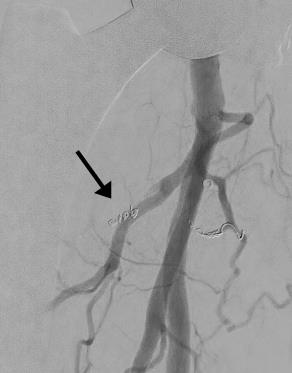

embolisation1

Embolisation einer Nachblutung nach Implantation einer Endoprothese an der rechten Hüfte